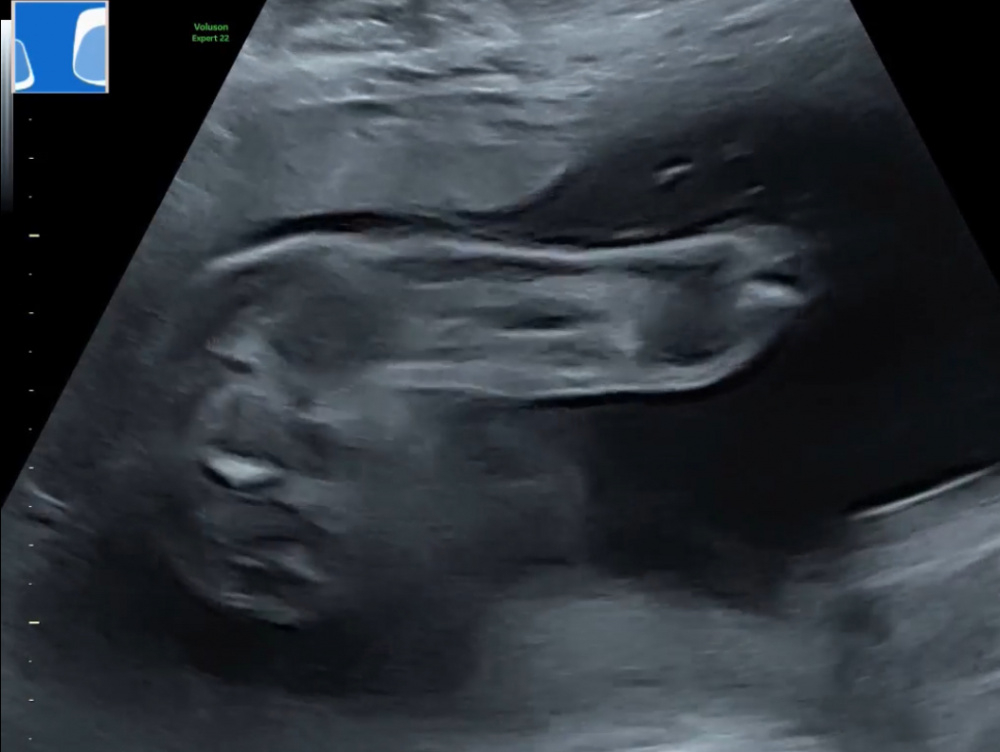

Hallöchen also wir haben beim Ultraschall diese Bilder bekommen und wissen nicht was das sein könnte. Ist das das Geschlecht und wenn ja, glaubt ihr eher ein Mädchen oder ein Junge ? Freue mich auf eure Kommentare

denke Mädchen da steht nicht s weg